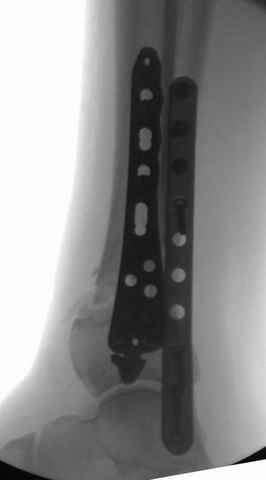

На снимках варианты фиксации малоберцовой:

№ 1 двух лодыжек